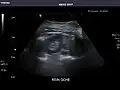

Right kidney -

Kidneys: Right and left kidneys measure 11.5 cm and 12 cm in length respectively. No hydronephrosis. Small left lower pole kidney cyst.